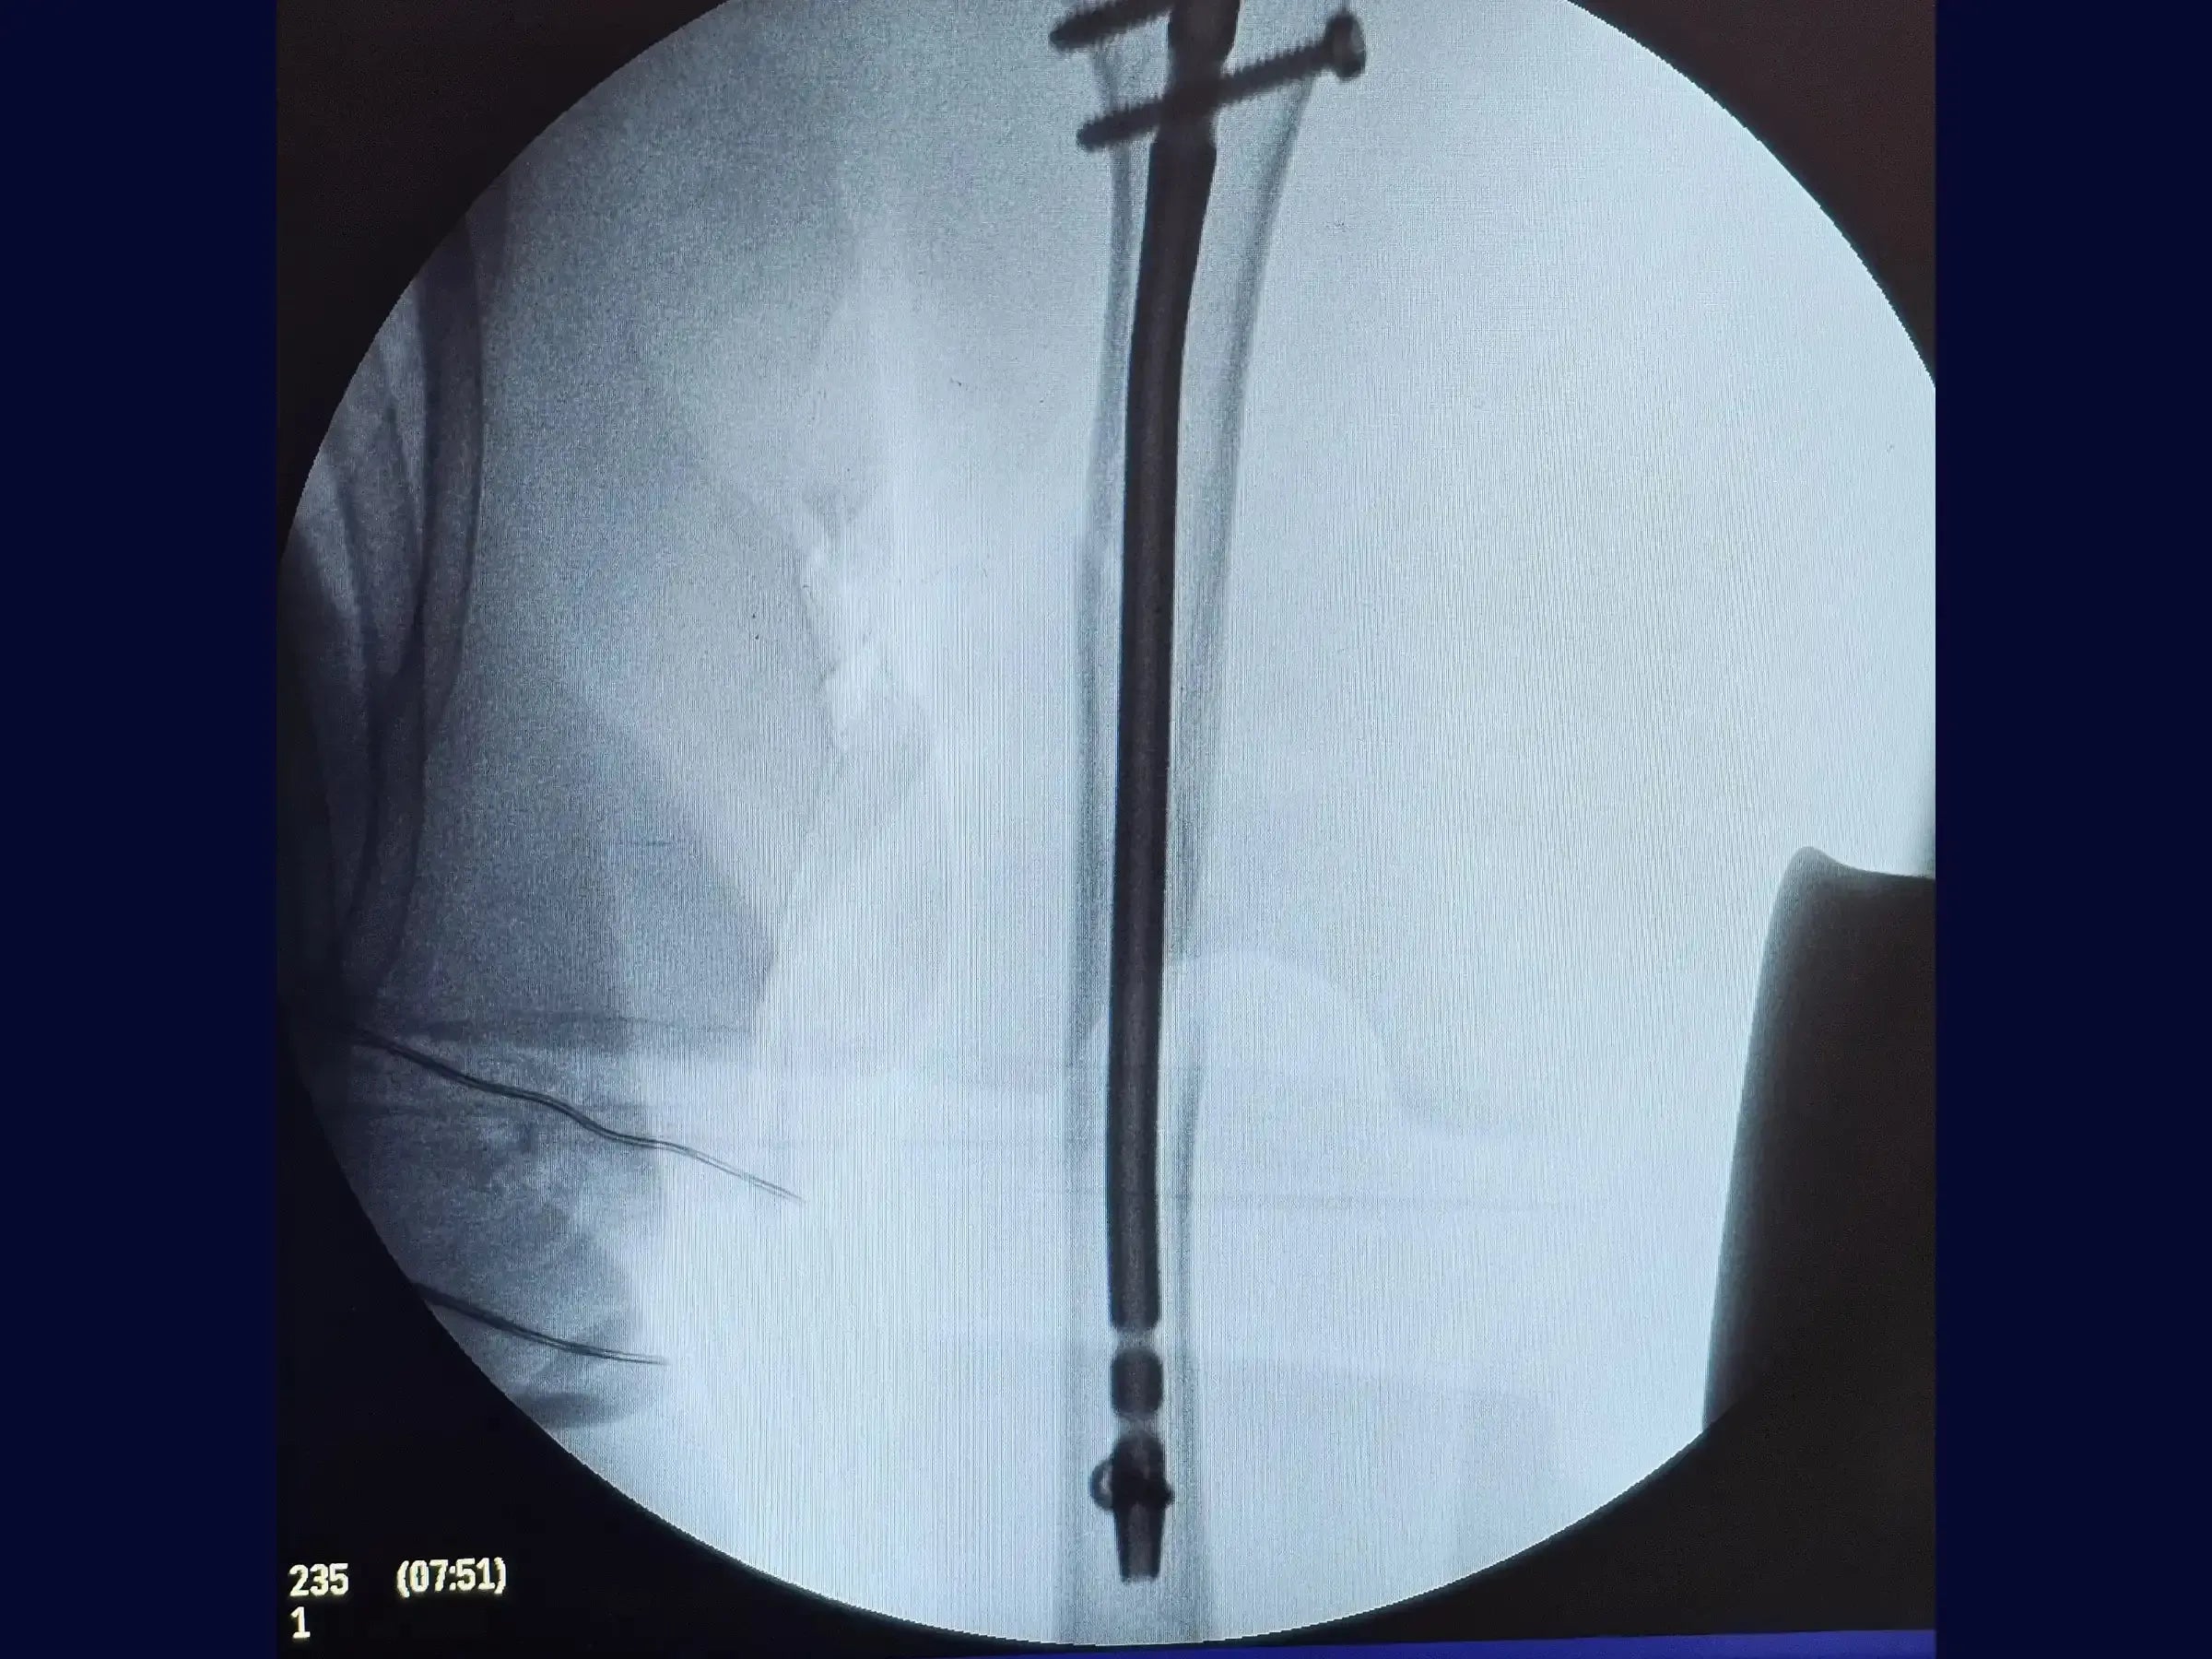

- Intramedullary nail fixation technique.

- High Difficulty Distal Blocking: Delve into the freehand distal blocking technique, a challenging procedure due to the triangular anatomy of the distal humerus. Understand the importance of using a sharp-tipped drill to avoid slippage and ensure the precision of the one-centimeter incision.

- Measurement and Insertion of the Intramedullary Rod: Develop the skill to measure the intramedullary rod accurately, considering the triangular tapering of the medullary canal to avoid protrusions and optimize the fit of the implant.